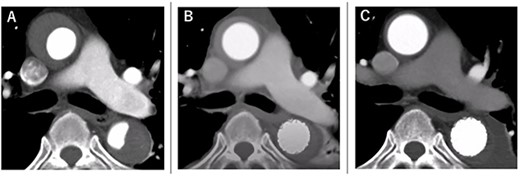

A 68-year-old man developed severe acute back pain and was diagnosed with acute type A aortic dissection with enhanced computed tomography (eCT) in the emergency department of our institute (Fig. 1A and B). The false lumen of the arch and ascending aorta was thrombosed (the maximum short diameter of the ascending aorta was 43.3 mm, the maximum diameter of the false lumen at the ascending aorta was 17.7 mm, Fig. 1C), and the primary entry was placed at the descending aorta. In addition, malperfusions were observed in the right renal artery and both iliac arteries (Fig. 1D). Therefore, we decided to perform TEVAR with the petticoat technique because of the rapid increase in true lumen blood flow.

eCT at diagnosis. (A): Sagittal view, (B) 3D reconstruction of the ascending and descending aorta, (C): Axial view of the ascending aorta and (D): 3D reconstruction of the abdominal aorta and iliac artery.